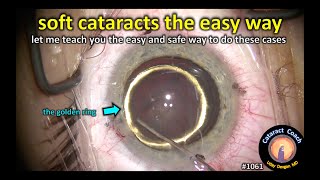

Dr. George Bahnan / Phacoemulsification 1052 CataractCoach 1061: soft cataracts the easy and safe way

CataractCoach 1061: soft cataracts the easy and safe way

Dr. George Bahnan / Phacoemulsification 1052 CataractCoach 1061: soft cataracts the easy and safe way

CataractCoach 1061: soft cataracts the easy and safe way